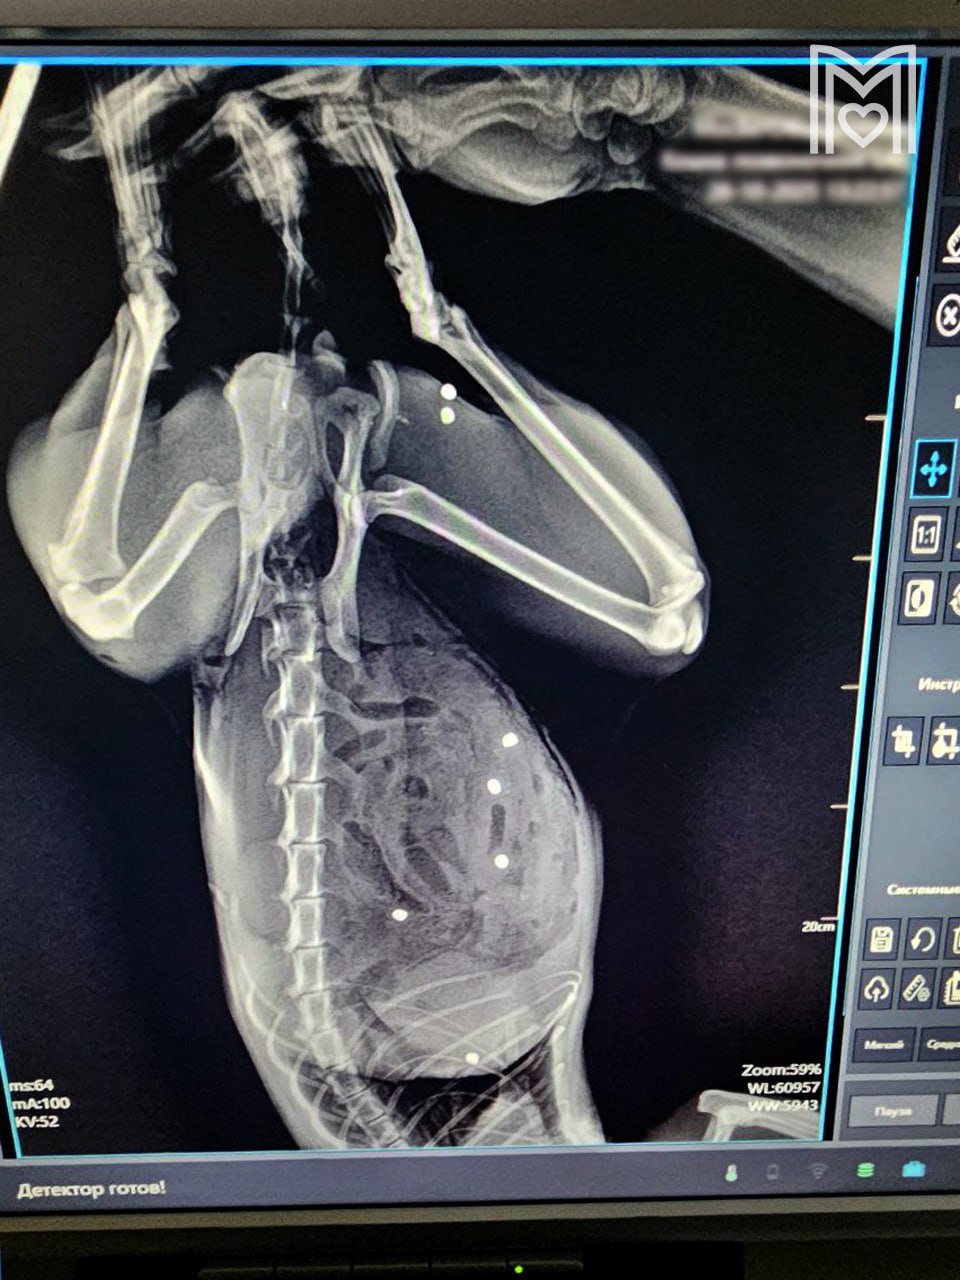

По словам врачей, Тимофей получил ранения в область груди и лап, что представляло серьезную угрозу для его жизни. Было зафиксировано не менее пяти пулевых отверстий. Шансы на выживание были минимальными, но благодаря самоотверженности врачей и стойкости самого кота, Тимофей выстоял. После операции Тимофей находился под круглосуточным наблюдением. Ему потребовалась интенсивная терапия, включающая в себя антибиотики, обезболивающие препараты и регулярные перевязки. Восстановление шло медленно, но верно. Каждый день приносил небольшие улучшения, вселяя надежду в сердца владельцев и врачей.